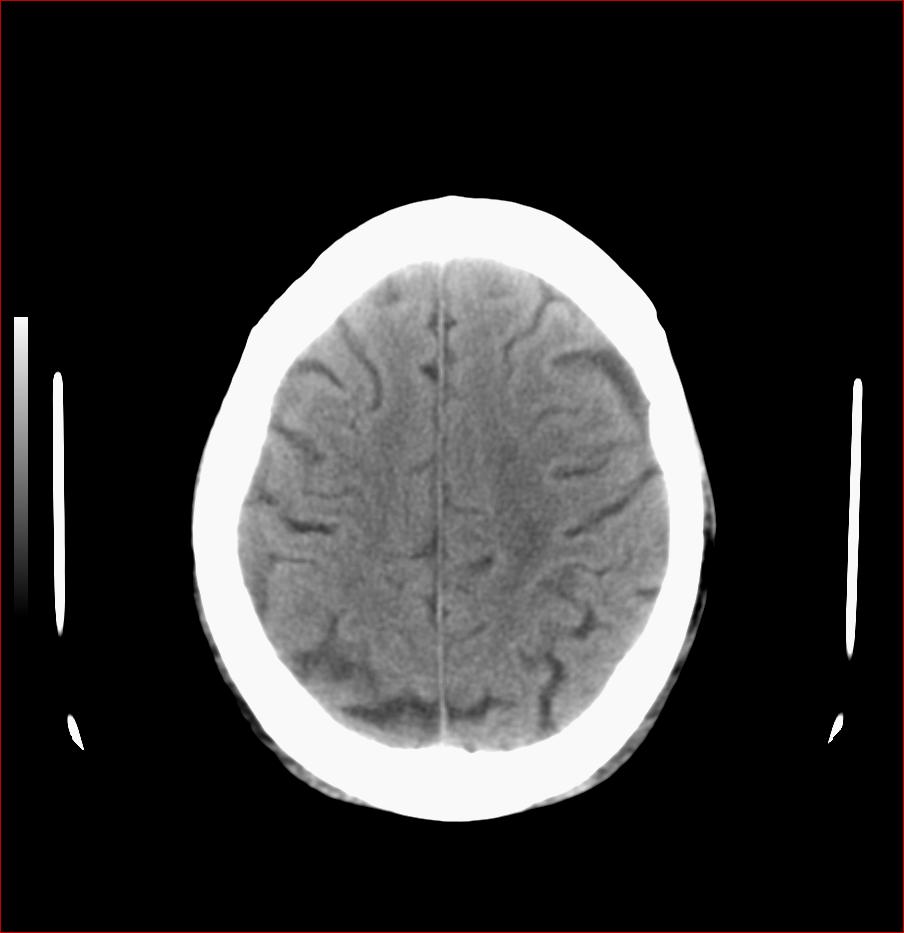

男,84岁,左下肢无力伴口角歪斜1天,血压160/80。请问一下双侧基底节区是脑梗塞吗?

双侧基底节腔梗,脑痿缩

基底节区脑梗塞,脑萎缩,左侧小脑脑梗塞

多发脑梗塞,白质疏松,脑萎缩

右侧基底节区斑片状低密度影,边缘模糊,结合临床考虑:1.右侧基底节区脑梗塞;2.老年性脑改变。

双侧基底节多发腔梗,皮层下动脉硬化性脑病

1.两侧基底节区及右顶深部脑梗塞。2.右侧外囊区脑软化灶。3.脑萎缩。4.脑白质脱髓鞘改变。

1.双基底节区及双顶深部脑梗塞;2.右外囊区软化灶;3.皮层下动脉硬化性脑病.